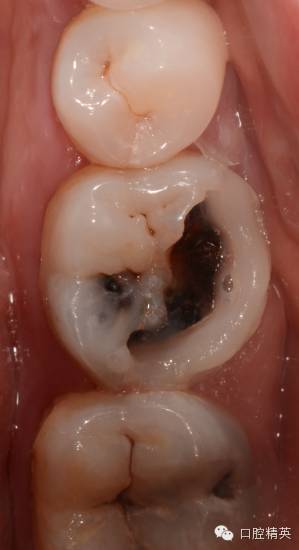

病例2:

患者女性,自诉左下后牙冷热不适两年多,昨夜疼痛加重,冷热水加重,疼痛累及头部及耳部,影响睡眠,今来诊,求治。

查:36颊he面及远中大面积龋坏,色黑质硬,探敏感,未探及穿髓孔,冷测持续性疼痛,扣无不适,不松,龈正常,对侧同名牙电活力测试值38,36电测牙髓活力值11。37颊侧龋,探敏感,未探及穿髓口,冷测一过性疼痛,扣无不适,不松,龈正常。

诊断:36慢性牙髓炎急性发作,37深龋

处:必兰阻滞麻醉下,36一次性根充,37树脂嵌体修复

36,37均有龋坏,且冷测敏感,很多时候我会使用牙髓电活力测试仪来判断牙髓状态,尽可能减少出现误诊,因为这种不可逆的操作,一旦出现误诊,对患者,对医生都是极大的痛苦。所以尽可能多种方法反复测试,如果实在找不到原因,时间也是一种方法。

颊侧龋坏较大,已经接近齐龈,于是树脂临时假壁修补,帮助橡皮障固定,也增加冲洗液容纳量

先清理干净准备做假壁区域的腐质,避免树脂沾接不牢在上橡皮障的时候假壁脱落,也避免漏液。